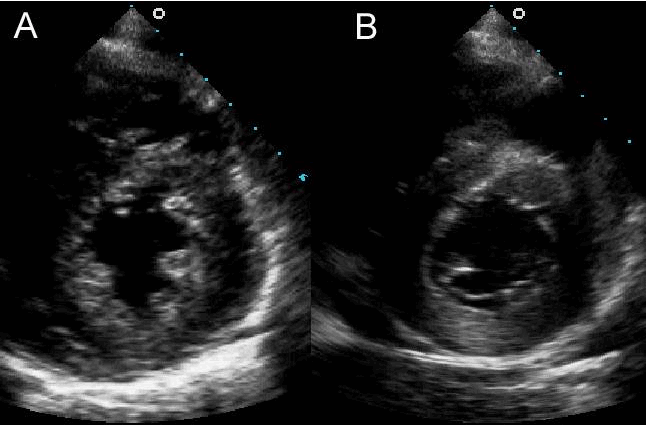

Những ảnh hưởng của tần số đầu dò khác nhau về chất lượng hình ảnh và sự xuất hiện được thể hiện. A: Một đầu dò 3.0 MHz được sử dụng để ghi lại hình ảnh trục ngắn. B: Cùng một hình ảnh được ghi lại bằng cách sử dụng đầu dò 5.0 MHz.